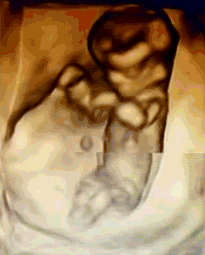

NT是胎儿颈部半透明扫描检查的缩写,是10~14孕周围绕在胎儿颈项后部流动性的半透明蛋白膜。它的厚度与胎儿DS缺陷正相关,并可以通过超声成像测量。NT检查便于及早发现唐氏儿、先天性心脏病和其他结构畸形的胎儿,并及时予以干预。

先进的机器设备是检查胎儿的重要辅助工具,在产检中有着至关重要的作用。安琪超声科早已引进多台美国GE-E8等系列仪器,能够更清晰、科学的检查胎儿的健康状况,满足从早孕期研究到复杂胎心的全程检查和诊断。通过四维立体成像,清晰并动态记录宝宝在子宫内的活动和成长历程。